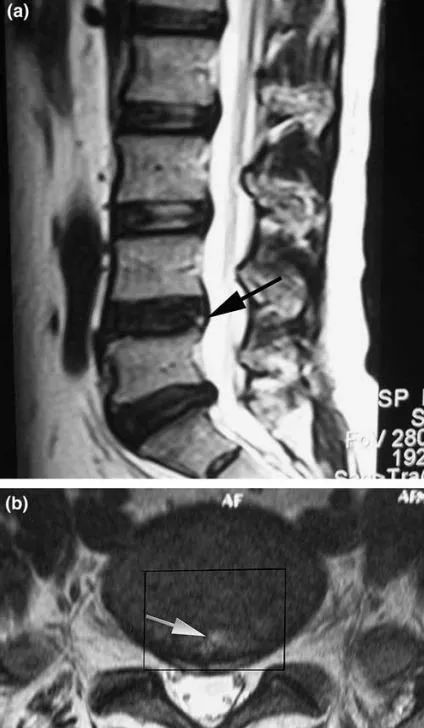

3.MRI 表现包括椎间盘含水量下降、纤维环龟裂、高信号区(HIZ)形成、椎间隙高度下降及终板形态改变。

高信号区域:指那些在 T2 加权像 MRI 上椎间盘纤维环后方高信号的部分。

椎间盘造影后CT平扫所显示破裂的纤维环,且造影剂流经至 HIZ 高信号区,提示椎间盘源性腰痛的诊断。

对于腰痛反复发作或伴有腹股沟区或双大腿前侧牵涉痛,无明显下肢神经根疼痛,持续时间久于 3 个月,MRI 表现为典型的单节段信号降低、纤维环后部出现高信号区(HIZ),应考虑为椎间盘源性腰痛。